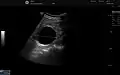

Renal ultrasonography of a simple renal cyst with posterior enhancement.

Renal cyst as seen on abdominal ultrasound

A very small (8 mm) simple renal cyst.